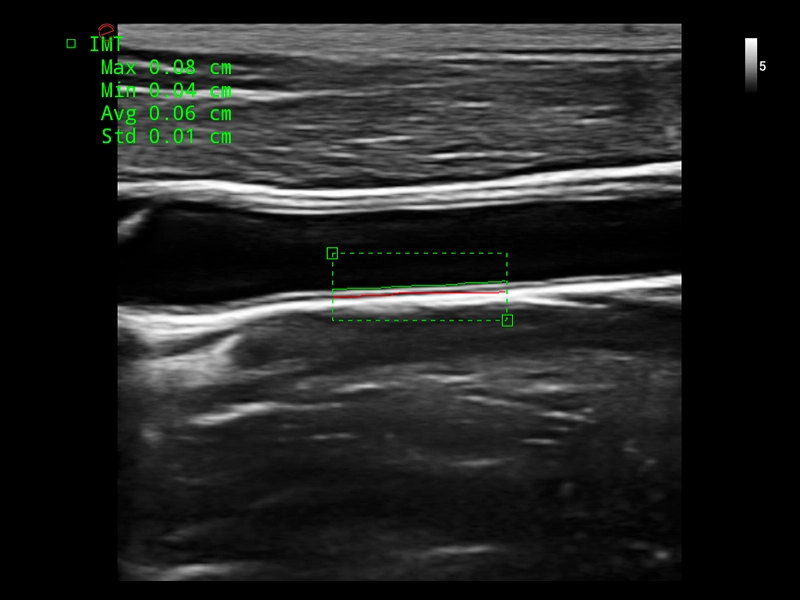

MyLab™X1 Go - Cardiovascular IMT

MyLab™X1 Go - Cardiovascular IMT